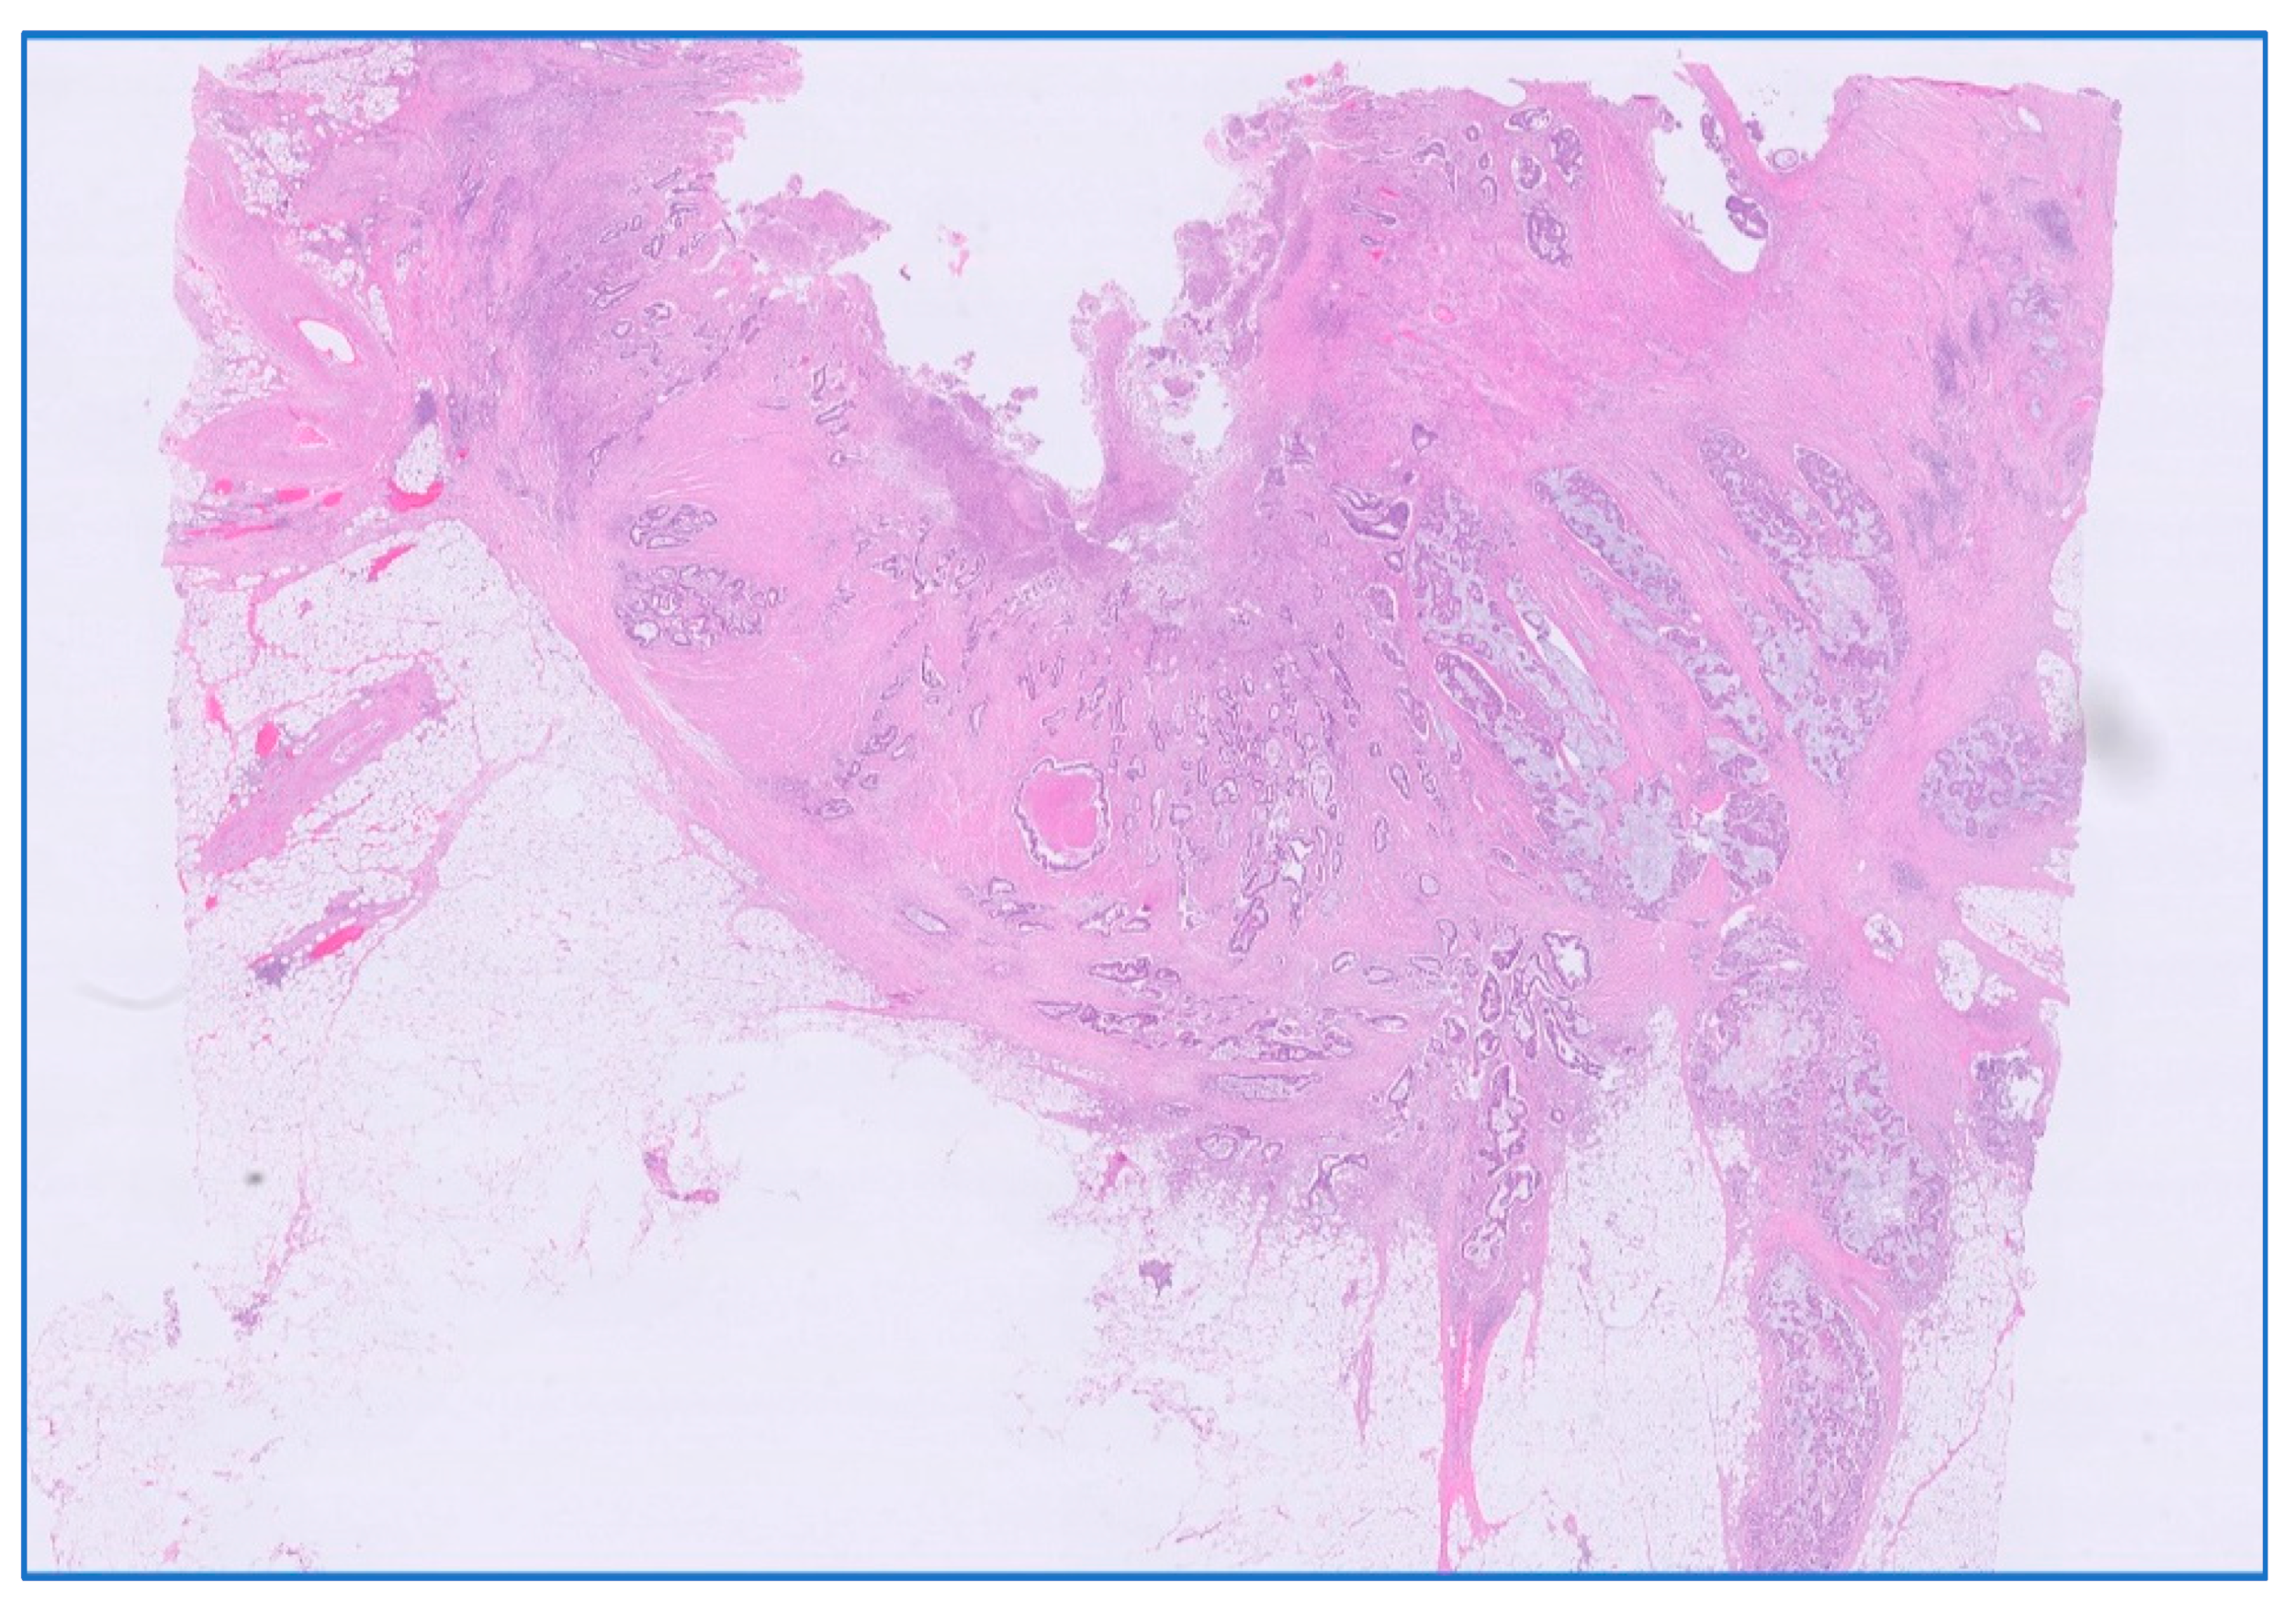

Standard neoadjuvant treatment, LCRCT, was positively correlated with the occurrence of tumor and nodal downstaging, with the latter being more significant with a correlation score of 0.436 and statistical significance at p < 0.001. RT alone given in neoadjuvant regimen yielded similar results for tumor downstaging, but weaker ones for nodal downstaging (Table 7, Figure 10).

Figure 10. Downstage of rectal adenocarcinoma after neoadjuvant LCRCT radiochemotherapy. Illustrated is a downstaged ypT1 with invasion in submucosa; HE stain × 10 magnification.